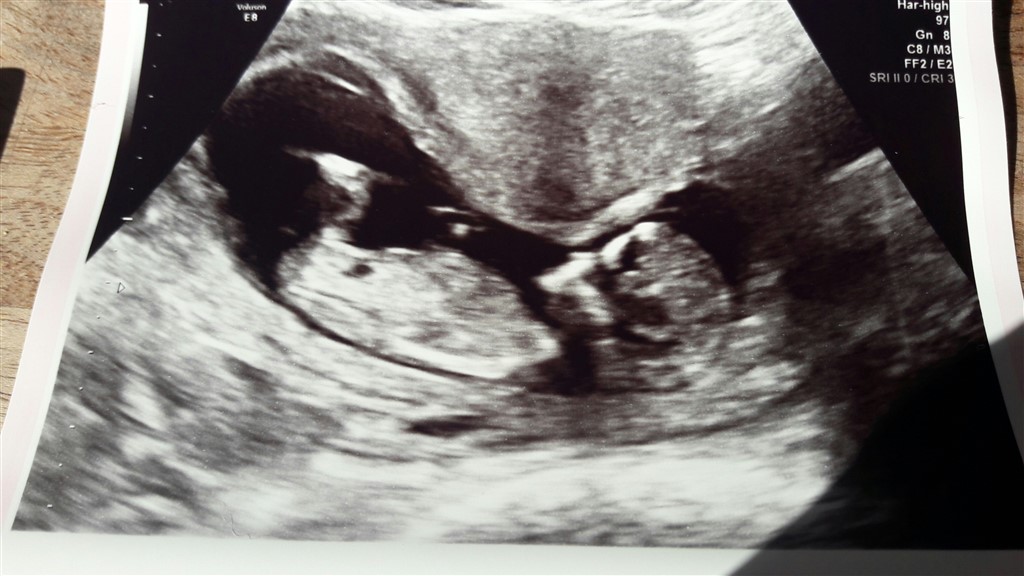

Så fik vi også overstået nf og det gik lige som det skulle. Baby har det godt og vokser som den skal, allerede næsten 10cm.

Jeg blev sat lidt frem, så er nu 12+1 (selvom vi jo ved præcis hvornår befrugtningen skete og jeg egentlig burde være 11+6), terminsdatoen hedder nu 2.11.17